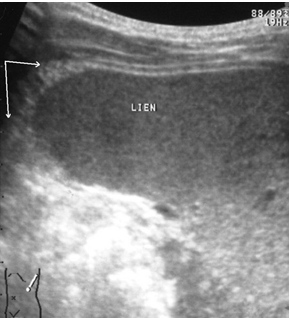

Ушибы селезенки сопровождаются интерстициальным отеком и геморрагическим пропитыванием тканей. Прямыми эхографическими признаками в первые 3–5 часов после травмы являются снижение эхогенности паренхимы и четкости контура органа, а также «разреженность» эхоструктуры паренхимы. Геморрагическое пропитывание паренхимы манифестировало наличием гиперэхогенных зон с нечеткими размытыми контурами в области повреждения (рис. 1). Характерно увеличение размеров всей селезенки или преимущественно поврежденного сегмента с нарушением ее конфигурации. Результаты цветового допплеровского картирования свидетельствуют о снижении кровотока, степень которого коррелирует с выраженностью эхографических проявлений отека паренхимы.

Рис. 1. Ушиб селезенки. Зона геморрагического пропитывания указана стрелками.